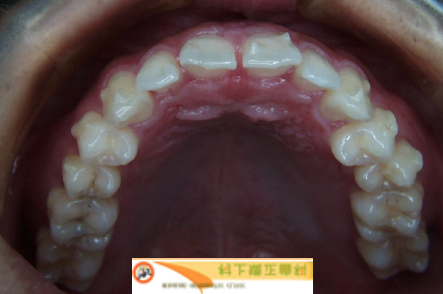

- Patient : 20y Male

- Case Type : Space Arch

- Aligner Type : Invisalign

- Treatment Time : 7 Month

①Upper side1

②Upper side2

③Upper side4

Upper side

上顎前突、正中離開の症例をインビザラインで7ヶ月で治療。1日22時間装着。